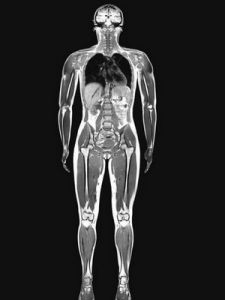

MR提供的信息量不但大於醫學影像學中的其他許多成像術,而且不同於已有的成像術,因此,它對疾病的診斷具有很大的潛在優越性。它可以直接作出橫斷面、矢狀面、冠狀面和各種斜面的體層圖像,不會產生CT檢測中的偽影;不需注射造影劑;無電離輻射,對機體沒有不良影響。MR對檢測腦內血腫、腦外血腫、腦腫瘤、顱內動脈瘤、動靜脈血管畸形、腦缺血、椎管內腫瘤、脊髓空洞症和脊髓積水等顱腦常見疾病非常有效,同時對腰椎椎間盤後突、原發性肝癌等疾病的診斷也很有效。

核磁共振的另一特點是流動液體不產生信號稱為流動效應或流動空白效應。因此血管是灰白色管狀結構,而血液為無信號的黑色。這樣使血管很容易軟組織分開。正常脊髓周圍有腦脊液包圍,腦脊液為黑色的,並有白色的硬膜為脂肪所襯托,使脊髓顯示為白色的強信號結構。核磁共振已套用於全身各系統的成像診斷。效果最佳的是顱腦,及其脊髓、心臟大血管、關節骨骼、軟組織及盆腔等。對心血管疾病不但可以觀察各腔室、大血管及瓣膜的解剖變化,而且可作心室分析,進行定性及半定量的診斷,可作多個切面圖,空間解析度高,顯示心臟及病變全貌,及其與周圍結構的關係,優於其他X線成像、二維超聲、核素及CT檢查。在對腦脊髓病變診斷時,可作冠狀、矢狀及橫斷面像。

核磁共振(MRI)已套用於全身各系統的成像診斷。效果最佳的是顱腦,及其脊髓、心臟大血管、關節骨骼、軟組織及盆腔等。對心血管疾病不但可以觀察各腔室、大血管及瓣膜的解剖變化,而且可作心室分析,進行定性及半定量的診斷,可作多個切面圖,空間解析度較高,顯示心臟及病變全貌,及其與周圍結構的關係,優於其他X線成像、二維超聲、核素及CT檢查。在對腦脊髓病變診斷時,可作冠狀、矢狀及橫斷面像。

MRI提供的信息量不但大於醫學影像學中的其他許多成像術,而且不同於已有的成像術,因此,它對疾病的診斷具有很大的潛在優越性。它可以直接作出橫斷面、矢狀面、冠狀面和各種斜面的體層圖像,不會產生CT檢測中的偽影;不需注射造影劑;無電離輻射,對機體沒有不良影響。MRI對檢測腦內血腫、腦外血腫、腦腫瘤、顱內動脈瘤、動靜脈血管畸形、腦缺血、椎管內腫瘤、脊髓空洞症和脊髓積水等顱腦常見疾病非常有效,同時對腰椎椎間盤後突、原發性肝癌等疾病的診斷也很有效。